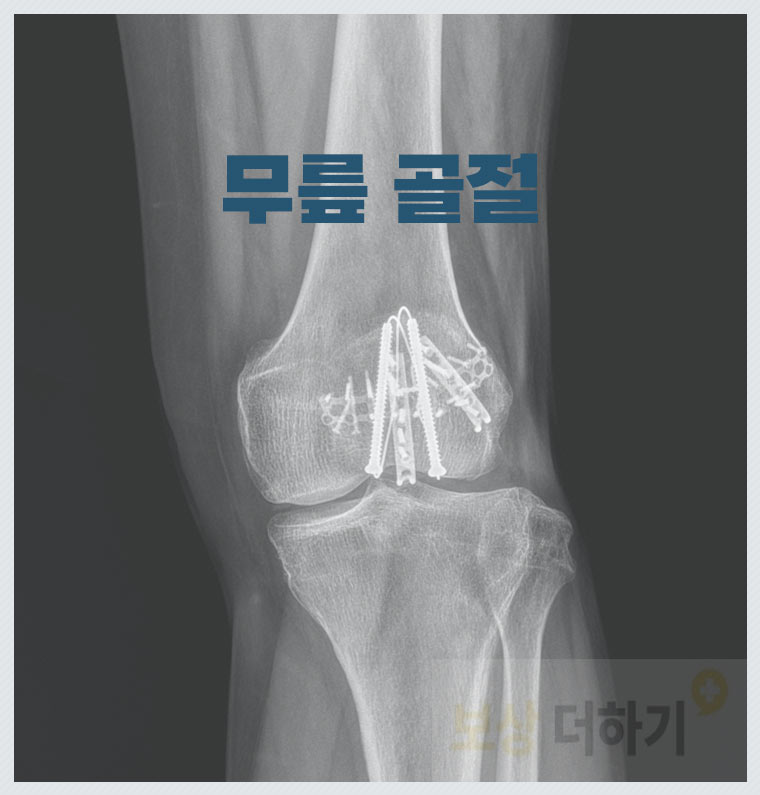

쇼핑몰 낙상사고 무릎 골절 (금속고정 수술) 피해 보상 후기

☞ S8200 무릎 골절 ☞ 내부 금속고정 수술 구급차를 타고 급히 내원을 하셨는데, 무릎 탈구를 동반한 혈종 상태였기 때문에 MRI 촬영을 통해 정밀한 검사를 하였습니다. 사고 당일 어긋난 뼈를 맞추는 정복 후 추가적인 수술 치료가 필요한 상황이었습니다.

위와 같이 금속고정 수술 즉 금속판, 나사를 사용하여 골절 부위를 고정하는 내부 고정술을 받았습니다.